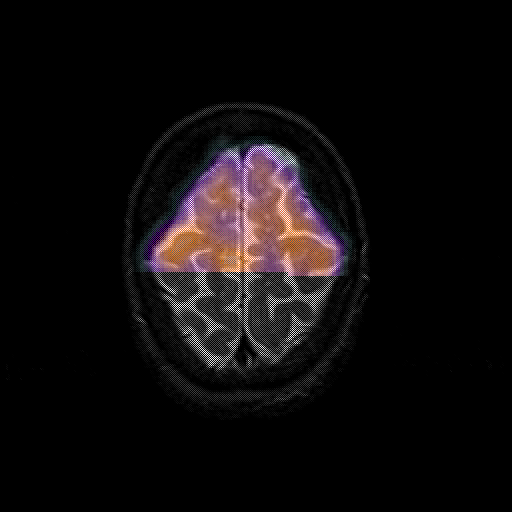

overlay 1: Slice 45

Slice 45

MRCBFCBF with

T1PDT2T1PDT2